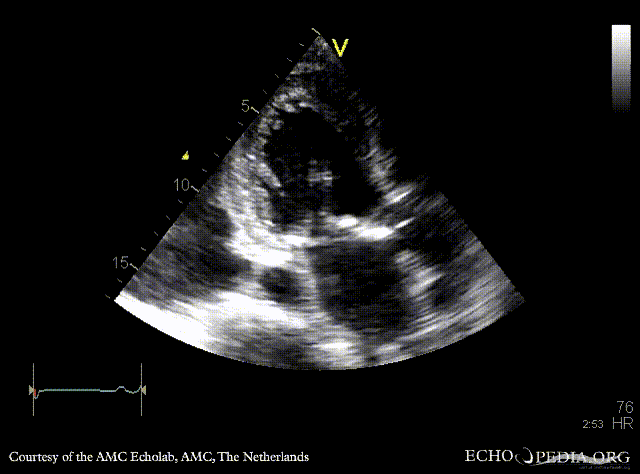

| A3CH: aortic bioprosthesis

| A3CH: Color Doppler, mild aortic regurgitation